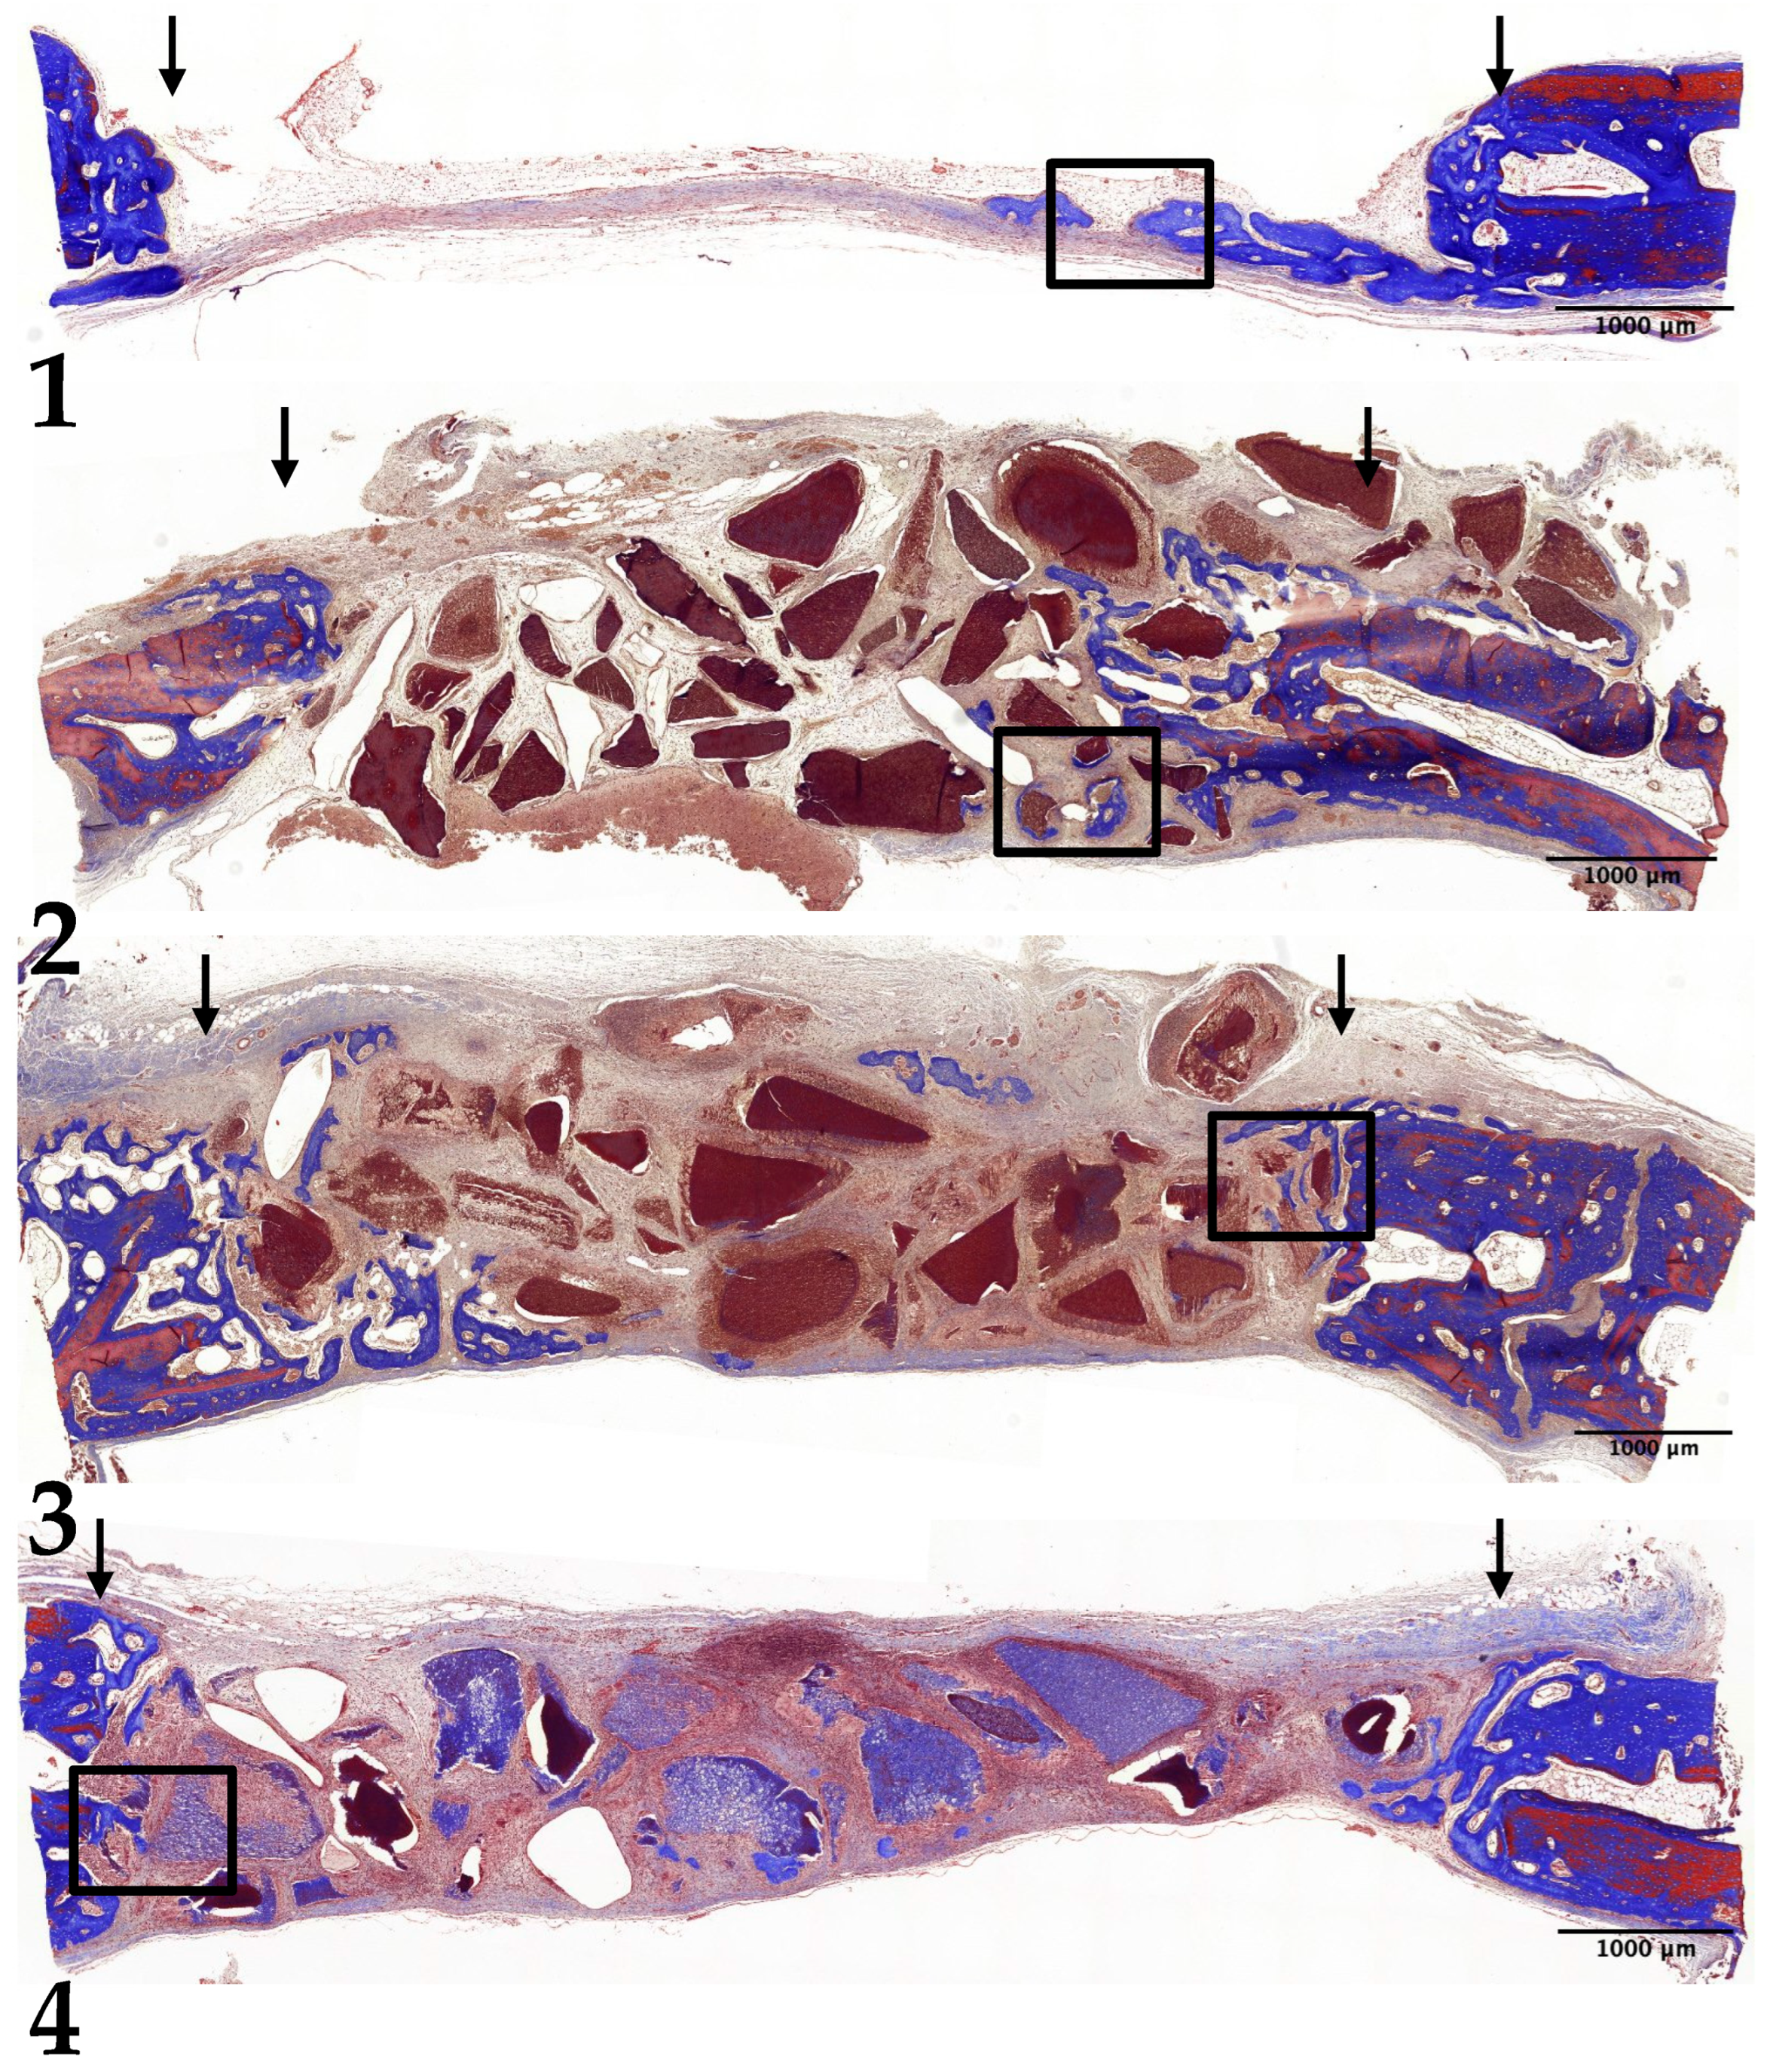

3.2. Two-Week Results

3.3. Four-Week Results

3.4. Eight-Week Results